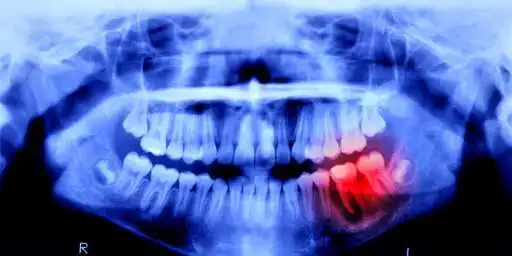

Humans May Be Able to Grow New Teeth Within Just 4 Years